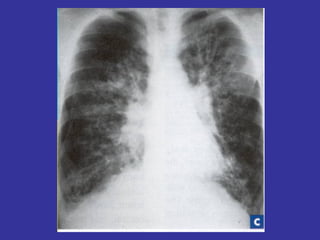

PNEUMONIA  Inflammation and infection of the lung parenchyma due to bacterial or viral  pathogens. Classified by anatomy:  Lobar, Interstitial, Bronchopneumonia Etiology: Viral:   Adenovirus, Influenza, RSV Bacterial:   Neonates:  GBS, Chlamydia, E. coli, Listeria monocytogenes  1month-6 years:  S. pneumonia, H. influenza Adolescents:  S. pneumonia, Mycoplasma pneumonia Immunocompromised:  Pseudomonas, klebsiela, Fungi, PCP

Epidemiology:   Children 2-4 years, are more susceptible than older children May follow epidemics of viral infection Winter/spring most common Day care/ kindergarten S/S:   Tachypnea,  dyspnea,  cough,  intercostal retractions, nasal flaring,  grunting,  fever,  accessory resp. muscles usage,  chest pain,  lethargy,  hypoxia, rales/crackles,  decreased  breath  sound/dullness to percussion (consolidation). LAB:   CBC:   WBC with left shift,  Blood culture (if severe picture),  Pleural fluid studies (effusion),  ABG  CXR:   Lobar consolidation ( S. pneumonia and H. influenza ),  Hilar adenopathy ( TB ),  Pneumatoceles ( S. aureus/G- ),  Bilateral diffuse infiltrate ( Mycoplasma ),  Abscess ( klebsiella ) Mycoplasma:  Presence of Cold agglutinin titers Prevention:   Pneumovax vaccine in immunocompromised children, SC Ds.

MYCOPLASMA PNEUMONIA